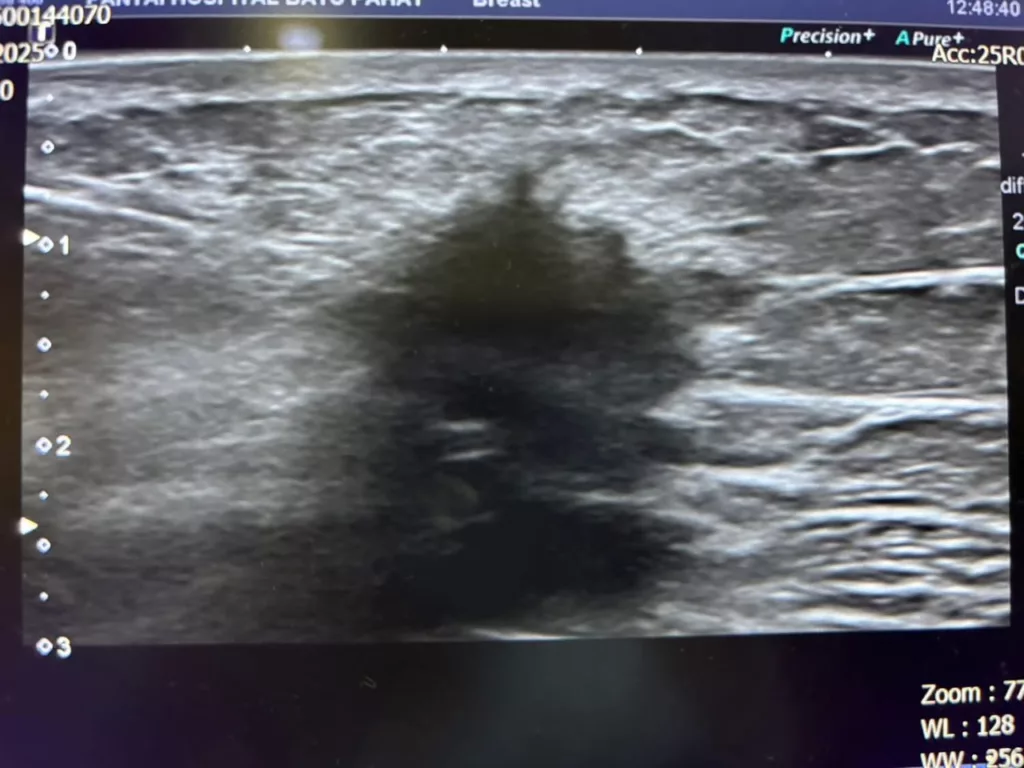

“Gambar ni adalah gambar ultrasound ketulan yg tumbuh di payudara. Memang nampak ciri kanser yang malignant dgn permukaan menggerutu (irregular outline). Gambar ultrasound guided biopsy menunjukkan jarum masuk dalam ketulan ambik sampel untuk dihantar ke makmal patologi. Pakar patologi akan baca slaid specimen untuk tahu apa ketumbuhan atau ketulan tu.”